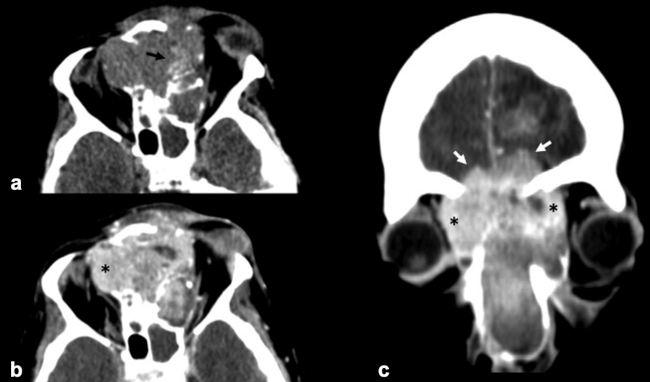

La TC de corte fino (espesor de corte de 1 mm) con reconstrucciones en plano coronal y sagital, es la mejor prueba de imagen inicial para el estudio del NBO. En la TC, aparece como una masa homogénea de tejido blando en la bóveda nasal con realce moderado y uniforme (►Figs.1y2). Se pueden encontrar calcificaciones punteadas dispersas (►Figs.2,3,4,5a,6).50 El valor principal de la TC es una mejor definición de la afectación ósea en comparación con la RM. La TC ayuda a evaluar la erosión ósea de la placa cribiforme, la fóvea etmoidal y la lámina papirácea (►Figs.1,2,3,4,5a,8). Sin embargo, la remodelación ósea sin erosión puede presentarse en algunos casos debido a su patrón de crecimiento indolente.3,35,49 Los estudios de TC generalmente revelan un patrón lítico y muy raramente hiperostosis dominante que simula displasia fibrosa.51 La TC también es útil para evaluar la presencia de metástasis regionales en cuello y a distancia.52,53

La RM es la prueba de imagen de elección para evaluar los detalles de la extensión y la estadificación locorregional del tumor. La RM es superior a la TC para determinar el grado de afectación del tejido blando (►Fig. 9) con una mejor evaluación de la afectación intracraneal (►Figs.10,11,12,13,14), orbital (►Figs.14y15), de la base del cráneo y la invasión perineural.53,54 La RM tiene un valor añadido para distinguir la afectación dural de la del parénquima cerebral (►Fig. 12).55 En la RM, el NBO aparece hipointenso respecto a la sustancia gris en imágenes ponderadas en T1 y de isointenso a hiperintenso en las imágenes ponderadas en T2 (►Figs.10,11,12,13,14,15).56 Muestra un realce homogéneo, excepto en áreas con hemorragia o necrosis. Además, permite diferenciar las secreciones retenidas del tumor, al ser estas hiperintensas ponderadas en T2.53,55 Los hallazgos de imágenes clásicos incluyen una masa “en forma de mancuerna” que se extiende a través de la placa cribiforme (►Fig. 12), con la parte estrecha a nivel de la placa. Los quistes tumorales periféricos (►Figs.5b,12,14,16) y las calcificaciones moteadas son bastante característicos de NBO.1

Las secuencias de RM con saturación de la grasa ayudan a diferenciar el tumor de la grasa orbital y los músculos. Un margen suave de la interfaz tumor-grasa sugiere que la lesión está contenida en la fascia periorbital (►Fig. 15), mientras que un margen irregular favorece la invasión franca de la órbita.35,49,57 Sin embargo, el diagnóstico definitivo de invasión de la duramadre y los tejidos periorbitarios solo es posible en la cirugía.49